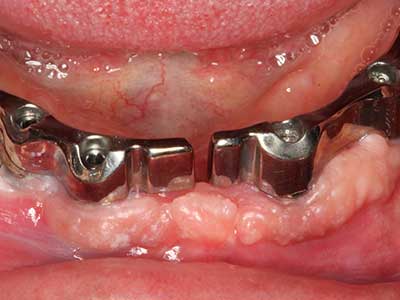

Fig. 18: Preparation of a cortical cover with the piezo bone saw (Piezomed, W&H).

Fig. 19: Surgical site after neurolysis and removal of osteoma.

Fig. 20: The removed bone cover is re-adapted and fixed with an osteosynthesis screw (KLS Martin, Tuttlingen).